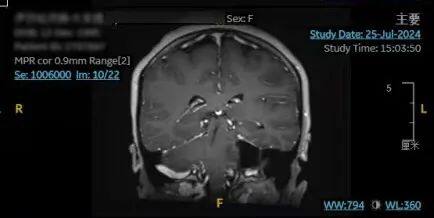

术后

术中,沈剑虹和神经外科主治医师姚麒在显微镜下小心翼翼地避开周围的血管神经,将肿瘤从中剥离;电生理监测医师刘倩倩配合实施神经电生理监测,跟踪面神经走行。在麻醉手术团队的密切配合下,伊孜颅内的听神经瘤历时6个多小时被精细、完整地切除,面神经功能也被成功保留。